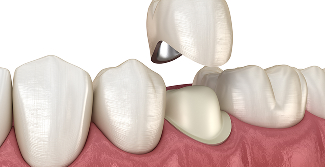

골드 크라운

치아와의 적합성이 뛰어나며, 씹는 힘이 강한 어금니에 적합합니다.

금속 재료이지만 생체 친화적이며, 잇몸 자극이 적습니다.

• 높은 강도

• 생체 친화적

지르코니아 크라운

강도가 높은 세라믹 소재로, 자연치아와 유사한 색상과

내구성을 가지며 치아와의 밀착력도 우수합니다.

• 뛰어난 심미성

• 자연스러움